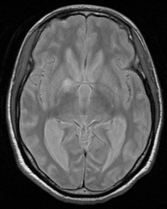

A 26-year-old man was admitted in our Rehabilitation Unit in May 2022 after being diagnosed with TBM. The patient presented to the emergency department with a 2-week history of fever, disorientation, decreased lower limbs strength and urinary incontinence. He had a recent history of contact with tuberculosis (TB), with a positive interferon gamma release assay test. Brain magnetic resonance imaging (MRI) with gadolinium contrast revealed hydrocephalus and diffuse leptomeningeal enhancement with basal cistern involvement (Figure 1). Acute ischemic brain lesions with hemorrhagic transformation in the right globus pallidus and anterior limb of internal capsule consistent with infarctions due to infectious arteritis, were also noted (Figures 2 & 3). Spine MRI with gadolinium contrast revealed diffuse cervical, thoracic, lumbar and sacral enhancement of meninges overlying the spinal cord and cauda equina nerve roots (Figure 4). These images were suggestive of TB infection. Blood cultures, serologies and cerebrospinal fluid (CSF) culture were negative for TB bacilli and he had no relevant medical history, including risk factors for being immunocompromised. Nevertheless, presumptive diagnosis of TBM was made in the setting of relevant clinical and epidemiologic factors in combination with typical CSF and MRI findings.

Figure 3 Brain MRI T2 images, axial view - acute ischemic lesions with hemorrhagic transformation in the right globus pallidus and anterior limb of internal capsule consistent with infarctions due to infectious arteritis.